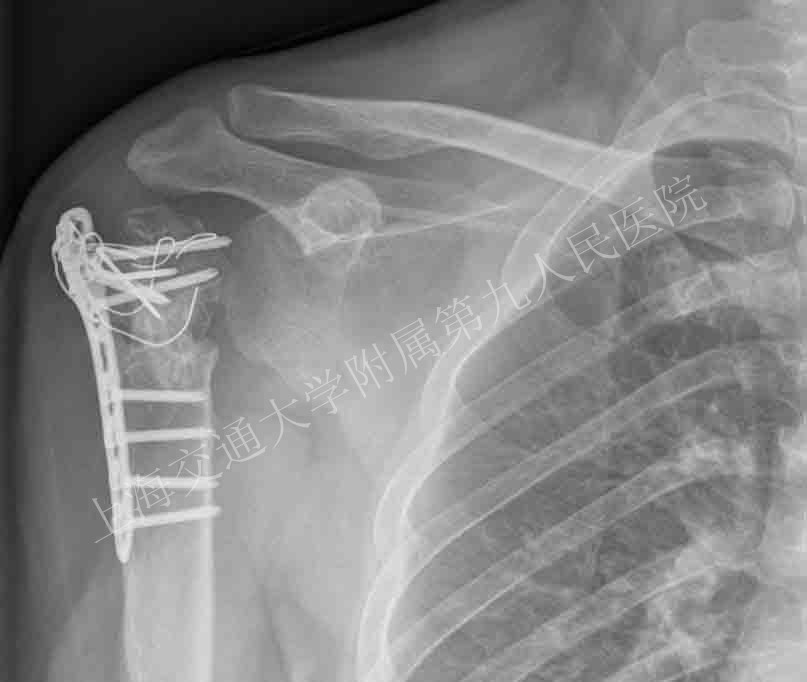

近期在戴尅戎院士领衔下,上海交通大学附属第九人民医院尝试将数字导板反式肩关节置换技术引入肩关节外科领域,该技术的应用对于在复杂的反式肩关节置换术中选择合适的假体以及调整假体后倾角和进行关节盂锉骨准备等操作中发挥很好的辅助作用。

术前照片